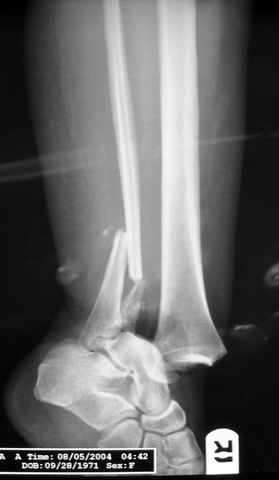

исходное

Re: ANKLE FRACTURE